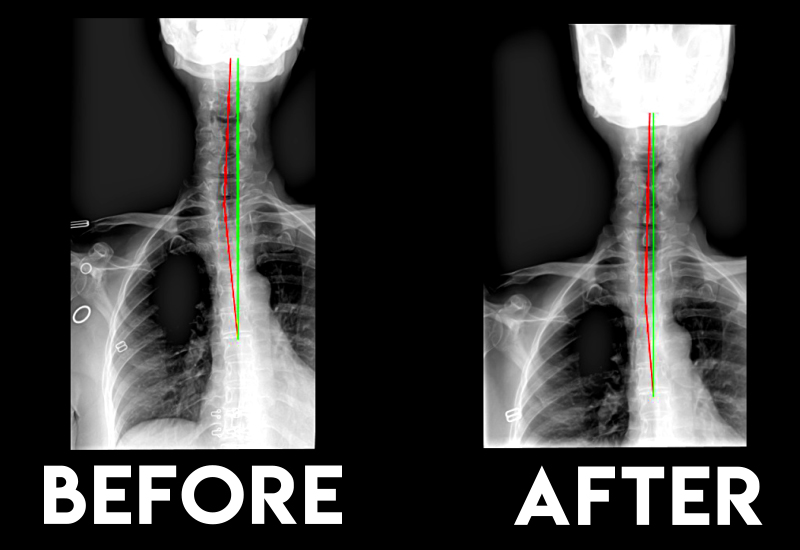

Neck pain

Better posture